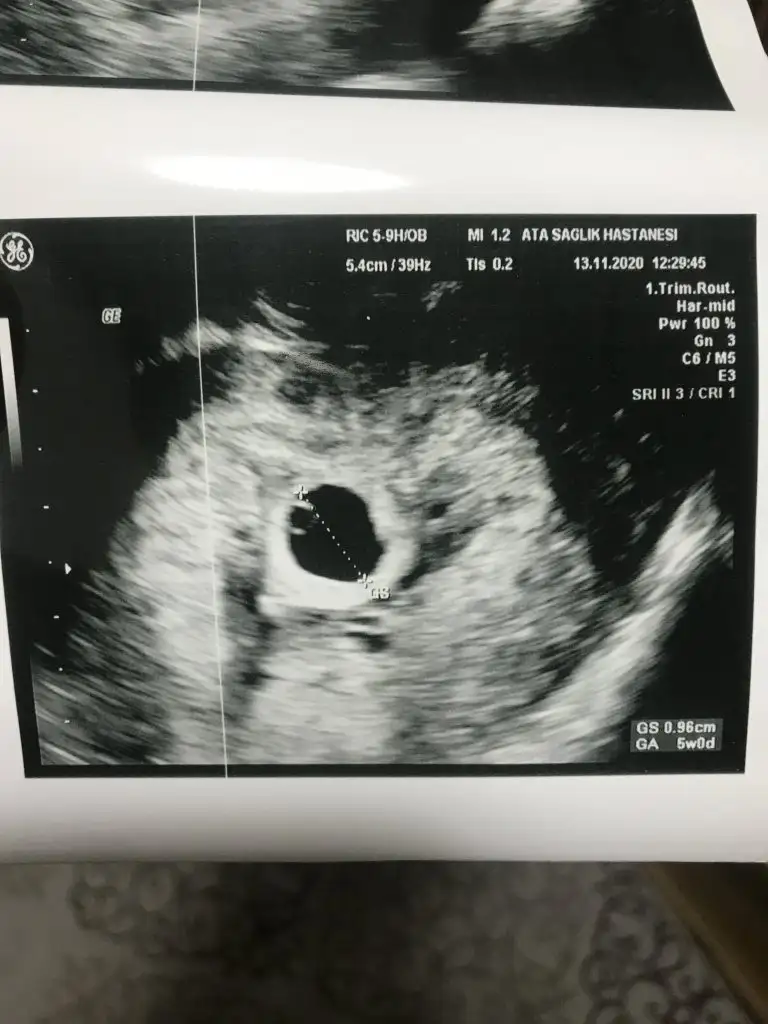

Benim 5haftalık usg resmi var olmaz dimi??Kese için 6-7 hafta nub için 11 12 13 haftalar olmalı

Paylaşın bakarımBenim 5haftalık usg resmi var olmaz dimi??

Vajinal usg resmi 5haftalık:)) nedir sizce ?Paylaşın bakarım

Buna göre kız gibi en iyi 11 12 13 haftalar olmalıVajinal usg resmi 5haftalık:)) nedir sizce ?